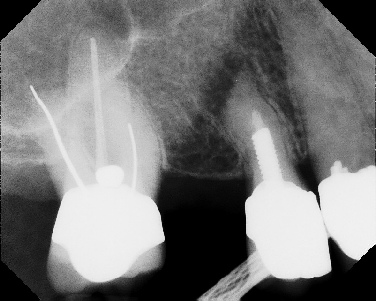

Apicoectomy - Surgical Root Canal Pre-op (post trauma) Coronal segments obturated Apical segments surgically removed 3 years